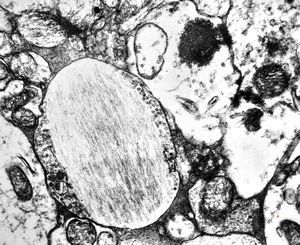

rabbit spinal cord trauma